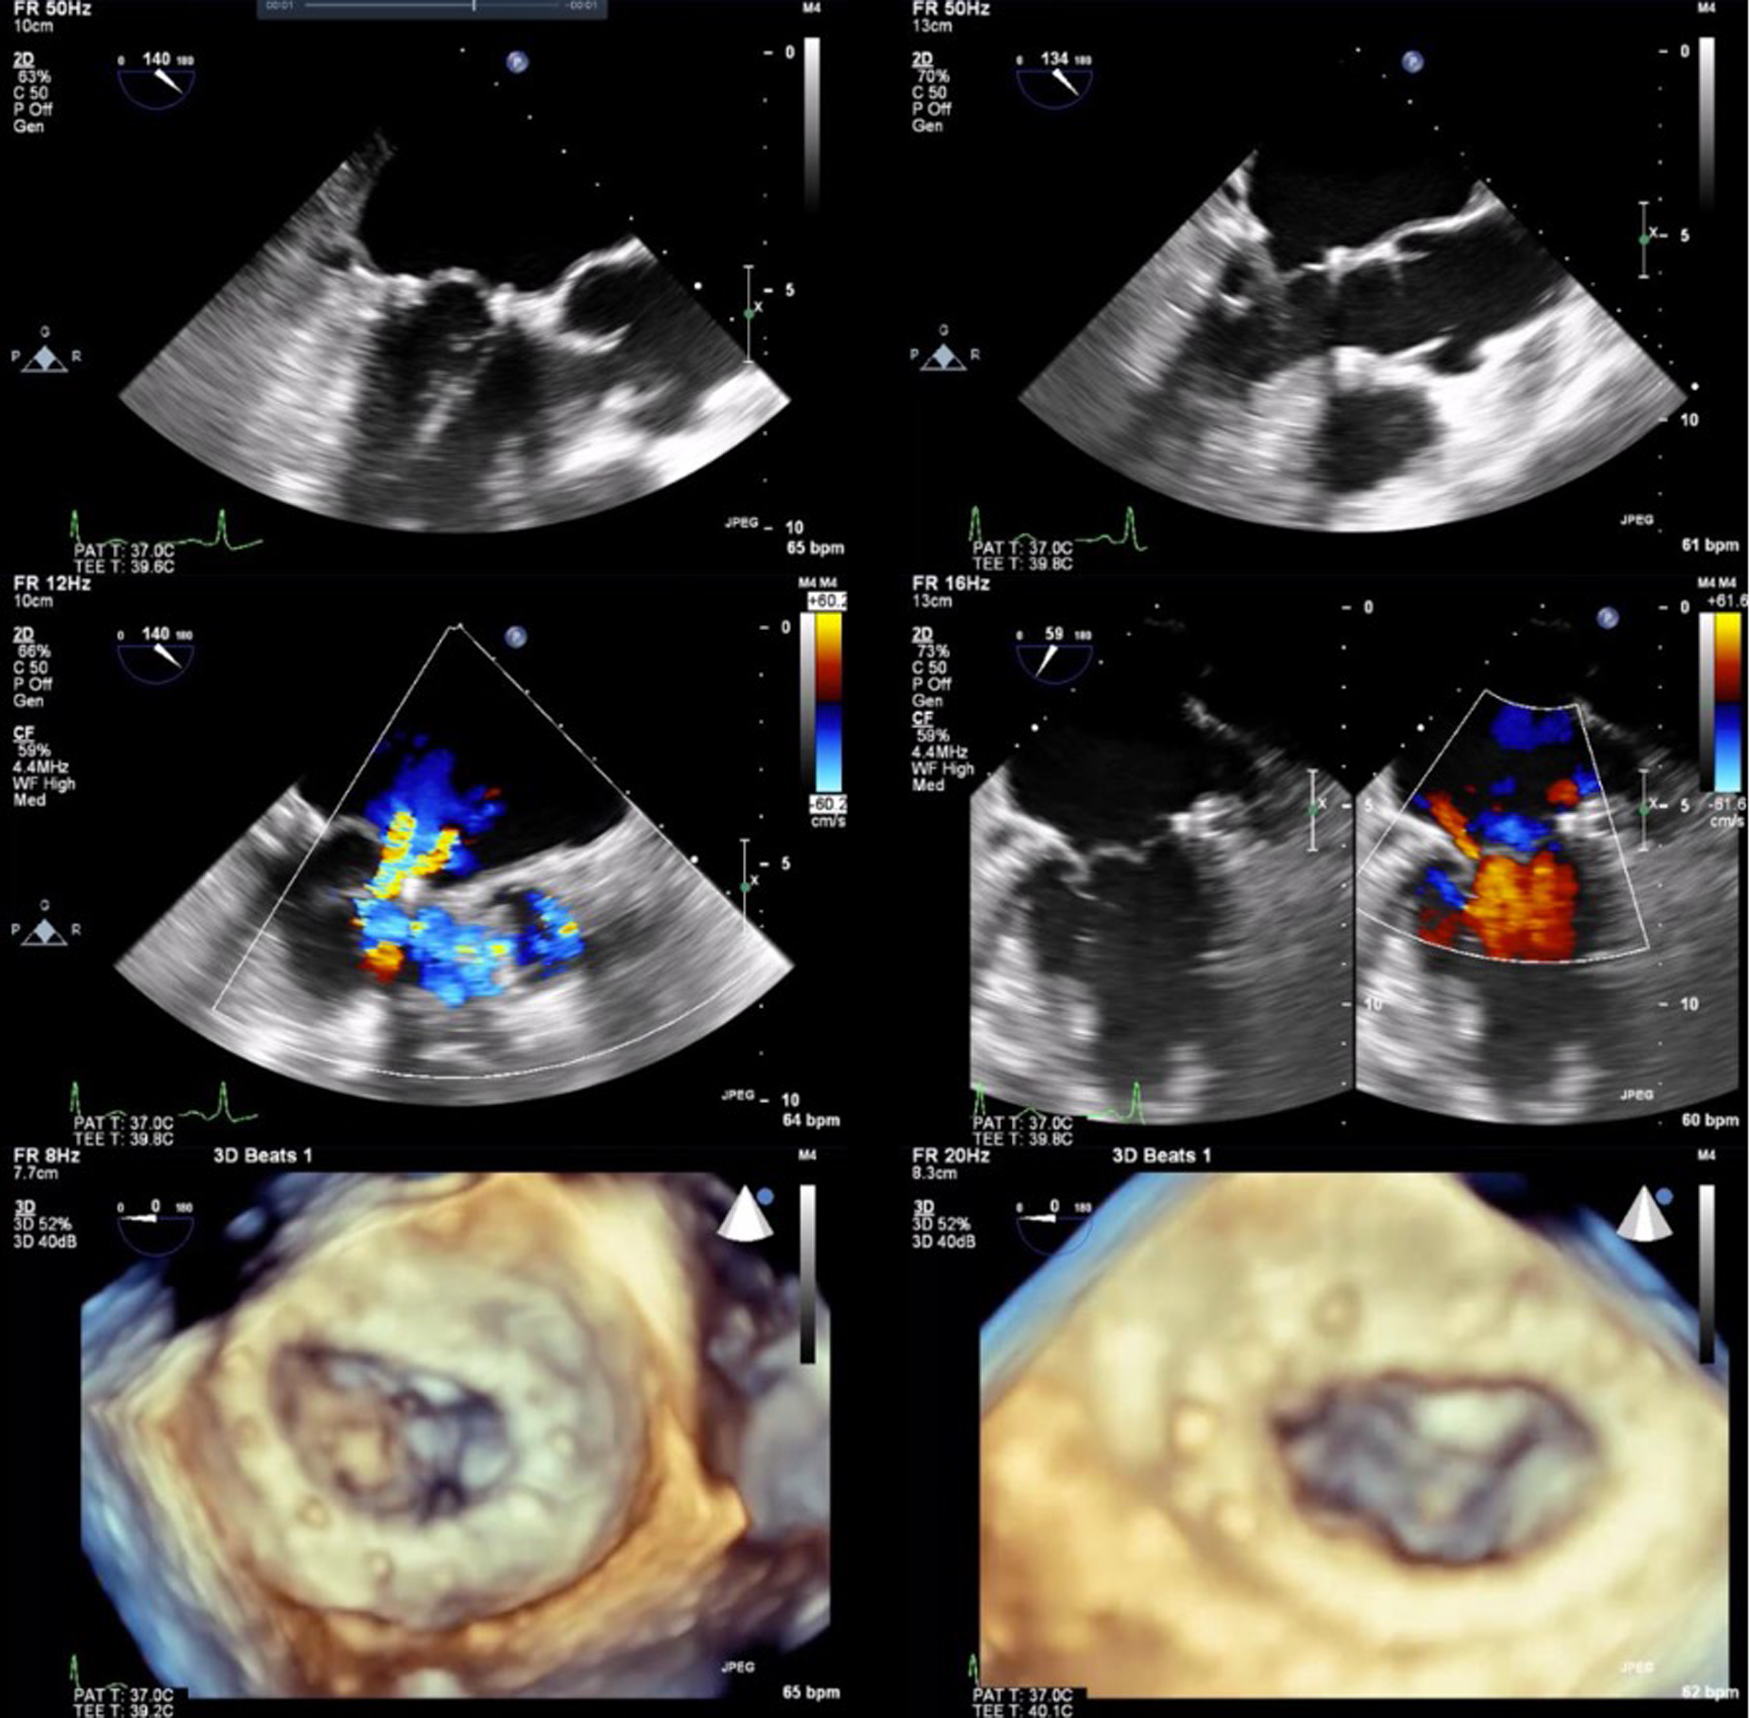

The NeoChord DS1000 was successfully implanted in 9 out of 10 patients transapically, with representative images in Figure 1. One patient required conversion to an open procedure for failure of the device to adequately grasp and deploy the chords. After sternotomy and cardiotomy with visual inspection of the mitral valve, the leaflet tissue was fragile and consistent with fibroelastic deficiency, with torn tissue from the device grasper. The patient required mitral valve replacement and was removed from further analysis of the NeoChord DS1000 procedural results.

FIGURE 1

www.frontiersin.org

Figure 1. Two and 3-dimensional view of preoperative images (left column) with P2 prolapse and severe MR. Post intraoperative delivery of NeoChord system and NeoChord tightening with mild residual MR (right column).